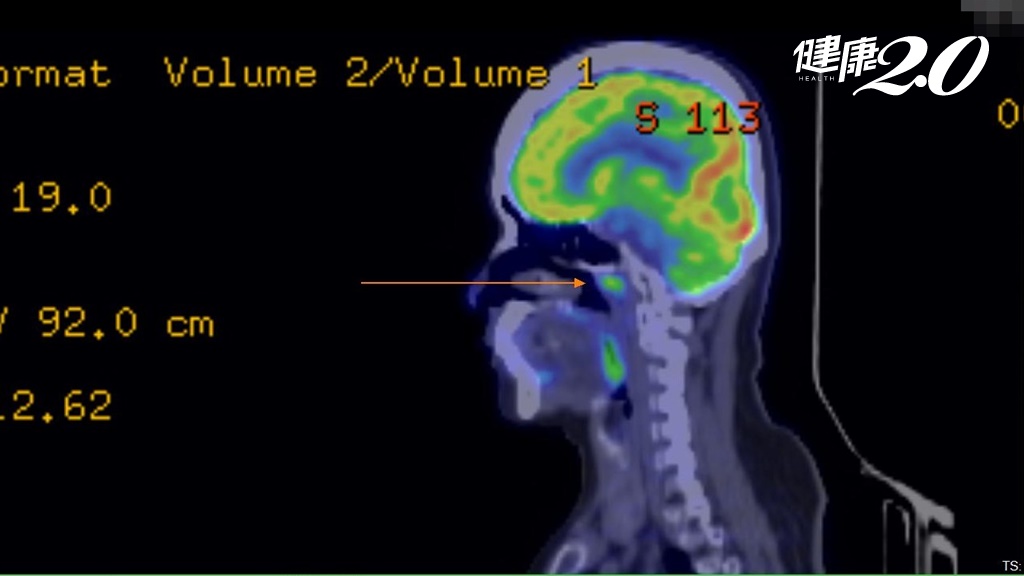

蔡若婷教授指出,質子治療最大特色就是「精準、副作用低」,將放射線劑量精準集中在腫瘤部位,高劑量消滅腫瘤,且幾乎不會對照射路徑上的健康組織造成傷害。此外,北醫質子中心使用的新一代超導型質子治療機配有筆型射束強度調控與3D影像導航等最新功能,有效減少治療副作用並提升病人的生活品質,治療後可以正常的生活。

北醫附設醫院放射腫瘤科主任暨北醫質子中心副主任李欣倫舉例說明,56歲王先生肺癌轉移腦部,先前治療副作用讓他備受煎熬,經以質子治療後,腫瘤獲得控制,還能恢復游泳、晨跑的習慣,展現質子治療「精準、副作用低」的特色,不僅讓病人活得久,而且要活得好。

萬芳醫院放射腫瘤科主任暨北醫質子中心副主任趙興隆表示,質子治療是放射治療的最新趨勢,最適合質子的癌症是兒科腫瘤、頭頸部及鼻咽腫瘤、攝護腺癌、骨盆腔癌復發等,目前也愈來愈多乳癌,尤其是左乳,以及縱隔腔癌、肝癌病人接受質子治療。根據國際文獻,相較傳統放射治療,質子治療對於腦部、脊椎、兒童癌症等特殊腫瘤治療,有較少的副作用及更多的應用空間。